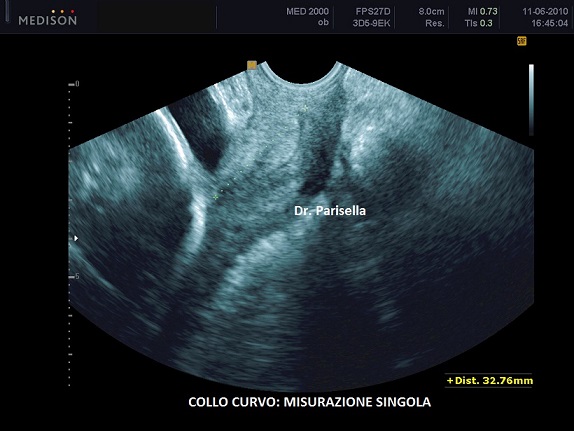

Se il canale cervicale non è diritto ma curvo la misurazione della CL viene effettuata in due fasi: si fa la somma di due linee rette che seguono la curvatura. In questo caso la scelta di effettuare una unica misurazione tra i due orifizi uterini o di ricorrere alla doppia misurazione dipende dal grado di curvatura; la tecnica è la seguente: si traccia una retta che congiunge i due orifizi uterini e si misura l'altezza tra questa retta e l'apice della curvatura; se la distanza è maggiore di 5 mm. si ricorre alla tecnica della doppia misurazione; se la distanza è inferiore a 5 mm. si misura direttamente la distanza tra i due orifizi uterini (vedasi immagini 1-2-3-4).